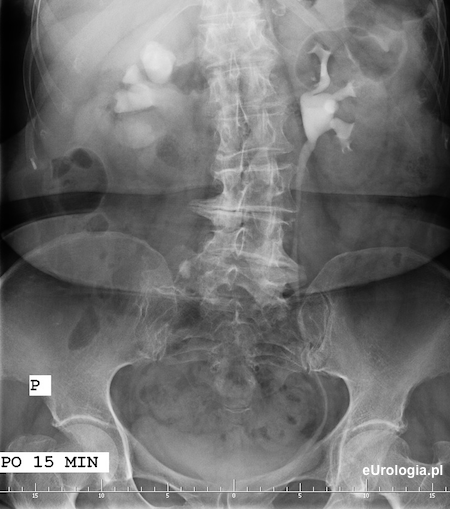

Zdjęcie po 15 minutach po podaniu kontrastu - wodonerczowato poszerzony UKM prawej nerki. Układ kielichowo-miedniczkowy nerk lewej i moczowód lewy na całej długości wypełnione zakontrastowanym moczem

Wodonerczowo poszerzony UKM prawej nerki i poszerzony górny odcinek moczowodu aż do opisywanego na zdjęciu przeglądowym cienia - złóg w moczowodzie.